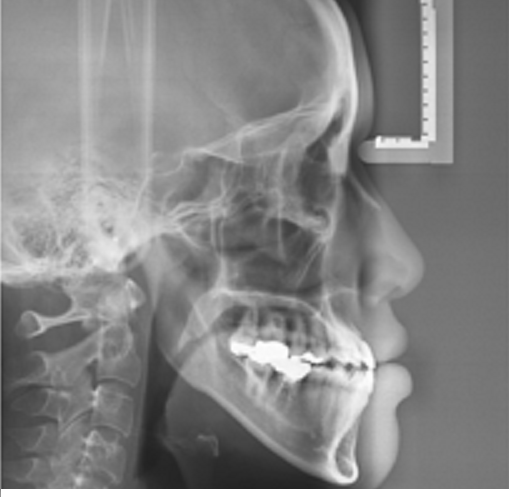

Ⅳ. 수술 병행 여부의 정밀 진단

위 사진들에서 확인할 수 있듯이

이분은 다행히도

1. 턱의 돌출과 안면비대칭이

심한 편은 아닙니다.

또한, 보편적인 주걱턱 분들의 경우

아래 치아가 안쪽으로 과하게 누워있습니다.

하지만 이분의 경우,

- 아래 치아가 많이 눕지 않은 경우

입니다.

- 아래 치아들 사이에

치아가 움직일 여유 공간이 존재.

- 1,2,3 번의 정확한 진단을 통해

학동역 세라믹교정

세라믹치과에서는

양악수술( 주걱턱수술, 악교정술) 없이

치아교정만으로

주걱턱 개선이 가능하다고 진단,

주걱턱 교정(세라믹 교정)을

진행하였습니다.